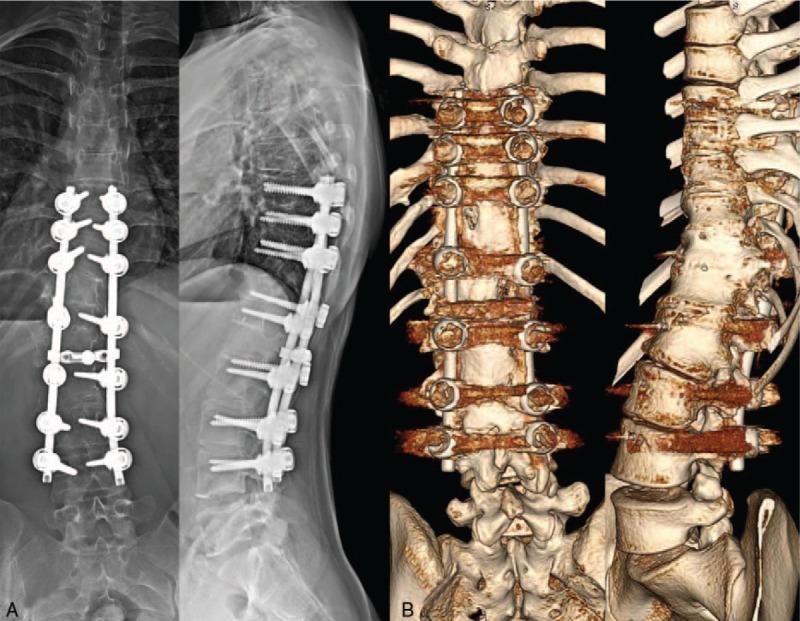

We report an 11-year follow-up of revision surgery for fractional curve progression after combined anterior and posterior fusion without hemivertebra resection using pedicle screw fixation (PSF) in congenital kyphoscoliosis at age 4 years (a total 18-year follow-up). A T12 hemivertebra was documented in a 4-year-old girl and was treated by combined anterior and posterior fusion in two stages with PSF. The fusion mass was maintained but the distal compensatory curve progressed during the follow-up period. The patient underwent a posterior vertebral column resection (PVCR) with extended posterior fusion at the age of 11, 7 years after initial surgery.

Eleven years after the revision surgery with PVCR, the patient showed satisfactory results and her spine was well balanced.

我们报告了一例4岁先天性脊柱后凸侧凸患者在未行半椎体切除的情况下采用椎弓根螺钉固定(PSF)进行前后联合融合术后因分节段曲线进展而进行翻修手术的11年随访情况(总计18年随访)。一名4岁女孩被诊断为T12半椎体,分两阶段采用PSF进行前后联合融合治疗。随访期间融合块保持稳定,但远端代偿性曲线进展。患者在初次手术后7年,即11岁时接受了后路脊柱椎体切除术(PVCR)及扩大后路融合术。

PVCR翻修手术后11年,患者效果满意,脊柱平衡良好。